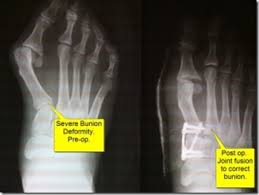

In order to get the best results from bunion surgery, it really helps to understand what happens during surgery and what to expect during the following days. Moy is the only bunion surgeon in the world who will post every before and after photograph as well as every evaluation on every single patient. A bunion is a firm bump that forms over a bony bulge at the base of the big toe. Lapidus bunionectomy and osteotomy tailor's bunionectomy performed with hammertoe correction of the 2nd toe. A bunion is a deformity of the foot that causes the big toe to turn inward toward the other toes.

Los angeles foot and ankle specialist dr. Bunion surgery including before and after pictures of bunion surgery. A bunion is a deformity of the foot that causes the big toe to turn inward toward the other toes. This is especially important since not all bunion surgeries are the same. Your results may differ from the before and after photos contained within this site. Fortunately there are many natural ways, including using the best the best bunion correctors can be the most effective way of reducing pain and friction so that you can easily perform daily activities like walking, running or. See more ideas about bunion, bunion exercises, feet care. Their formation is triggered by influenza, tonsillitis, gout, poor metabolism, improper nutrition, rheumatic infection and wearing uncomfortable shoes. Don't forget that if your bunions look awful and are causing huge pain, exercise or any other remedy won't work! After eight to ten weeks they may start to do an elliptical machine or more weight bearing exercises. Bob baravarian discusses the different types of bunion surgeries including the lapidus bunionectomy and how to chose a bunion surgeon. Try these bunion exercises for before and after surgery, follow easy instructions & learn how to perform movements safely and effectively. Foot exercises and toe stretches for bunions can help keep the joint between your big toe and the rest of your foot mobile, maintaining flexibility and strengthening the muscles that control your big toe.